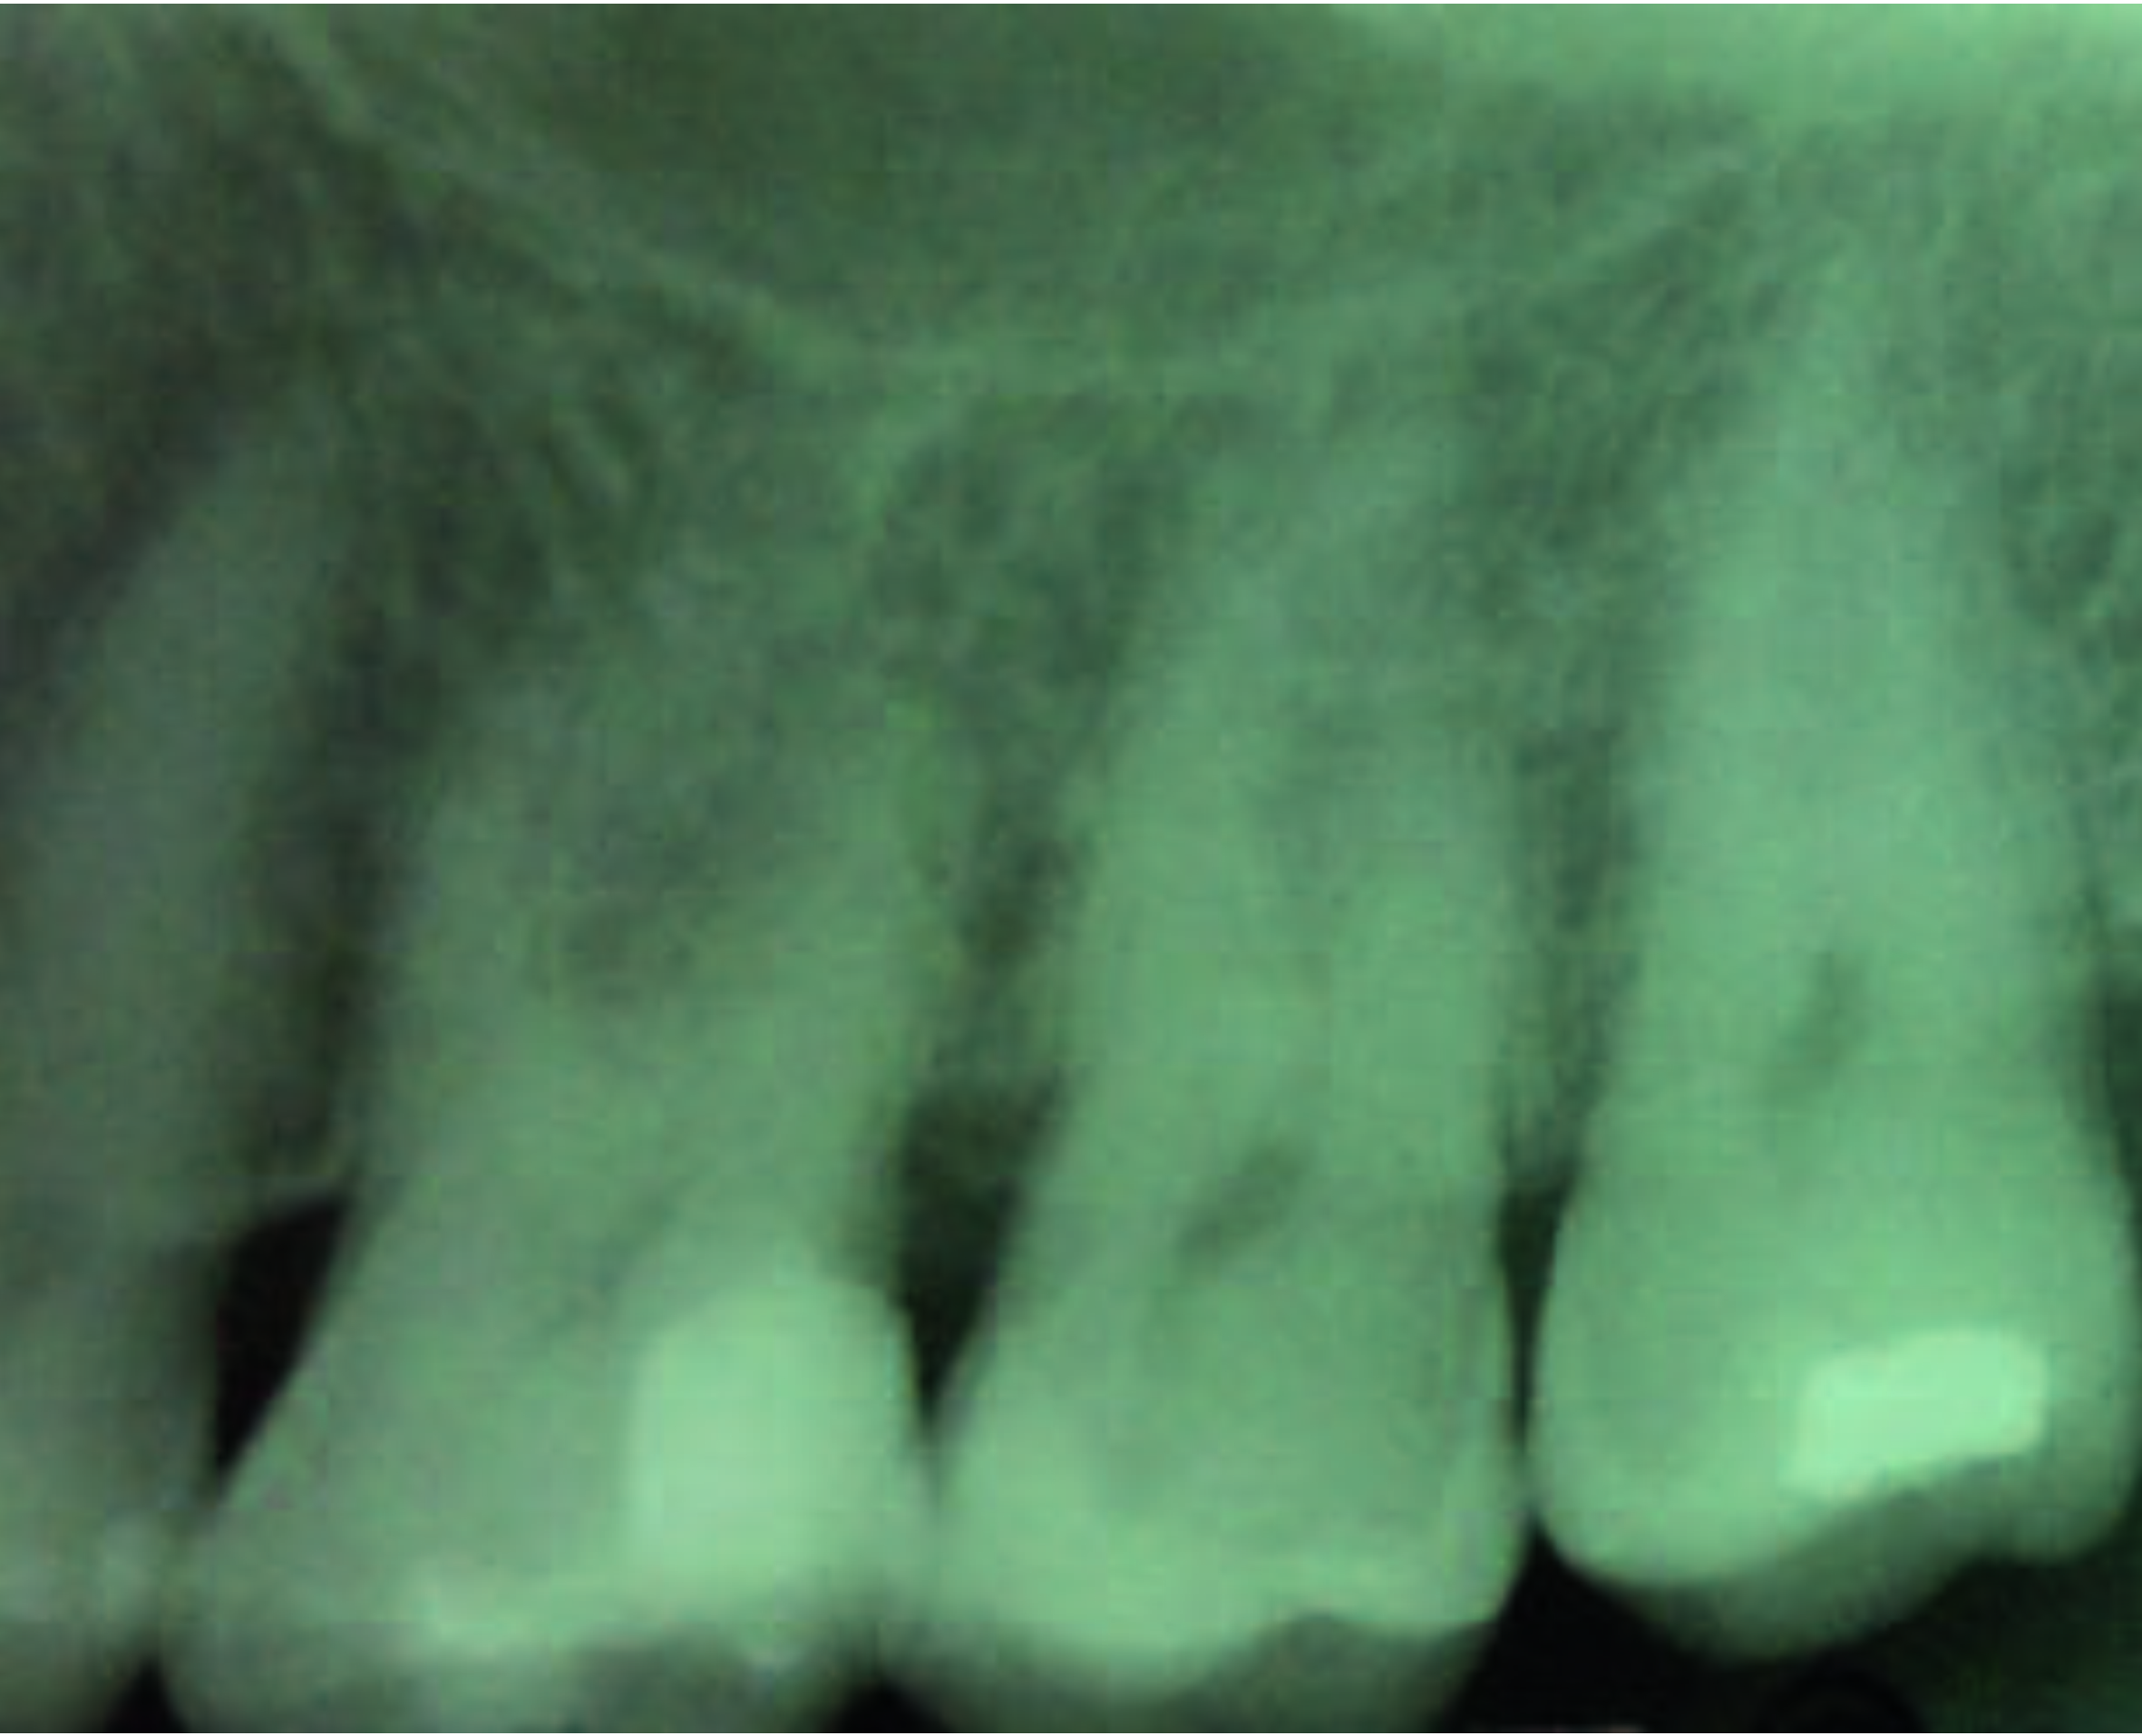

Фото 1.

Рентгенограма, зроблена до лікування.